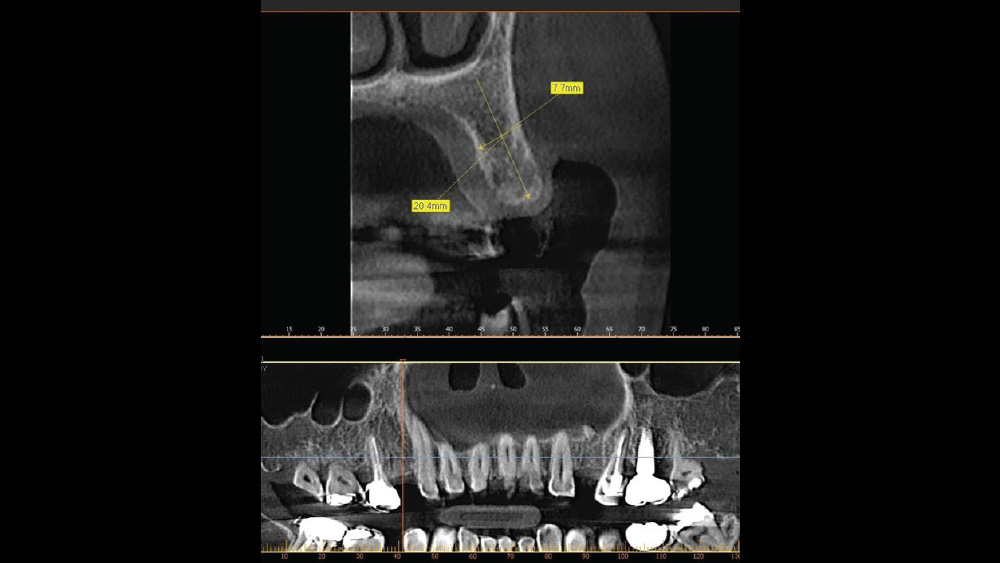

After gaining a clear understanding of the available hard and soft tissue through intraoral evaluation, radiography and — when possible — CBCT scanning, the clinician can determine whether flap reflection or a flapless surgical procedure is ideal for the individual patient. Both of these surgical techniques offer advantages, and the approach should be determined based on the amount of attached tissue present at the implant site, as well as the volume of bone.